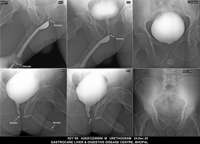

Section: URETHROGRAM

Total: 95 Cases